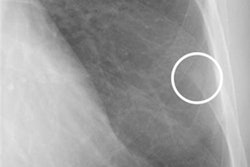

A 79-year-old male with mild COPD. Projected lung areas (PLA) of (a) tidal inspiratory phase and (b) forced inspiratory phase. Image (a) describes manually located white dots in the left lung field, which were used for automatic calculation of left PLA. Curve graphs describe the temporal change of PLA by automated tracking in (c) tidal and (d) forced respiration. Approximate straight line during forced expiration is colored purple. Image courtesy of the European Journal of Radiology.PLA in the forced expiratory phase was also different, with a statistical significance between COPD mild and COPD severe groups in the left lung (p < 0.001). In addition, changes in PLA in tidal breathing were lower in normal subjects than in COPD patients (p < 0.001), while changes in PLA in forced breathing were higher in the normal group than in the COPD severe group (p = 0.013), according to the findings.